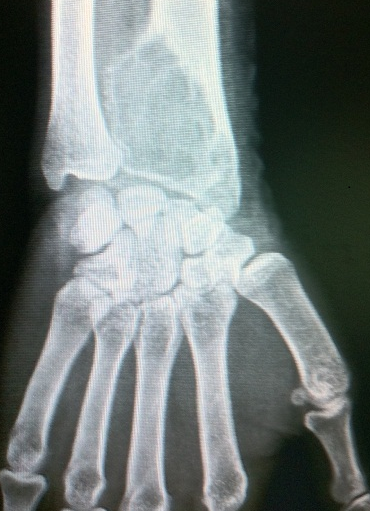

Le conflit radio-ulnaire distal résulte d'un pincement de l'articulation radio-ulnaire occasionnant un syndrome douloureux du poignet. Le conflit radio-ulnaire distal est le plus souvent d'origine dégénérative ou post-traumatique avec une atteinte du complexe triangulaire fibro-cartilagineux et un conflit ulno-lunaire associés par une inversion de l'index radio-ulnaire. Nous rapportons un cas de conflit de l'articulation radio-ulnaire distal chez une patiente de 35ans, secrétaire de profession, consultant pour des douleurs chroniques du poignet gauche. Une radiographie du poignet en incidence de face objectivait une volumineuse lacune de l'extrémité inférieure du radius épiphyso-métaphysaire, bien limitée, aux contours irréguliers, d'aspects multi-cloisonné « soufflant l'os » sans rupture de la corticale osseuse du versant interne. Cette lésion expansive envahissait la membrane interosseuse et entrainait un conflit radio-ulnaire. La biopsie osseuse a été effectuée et revenait en faveur d'un kyste anévrysmal osseux. Le traitement chez notre patiente a consisté à un curetage des cavités kystiques associé à une greffe osseuse.